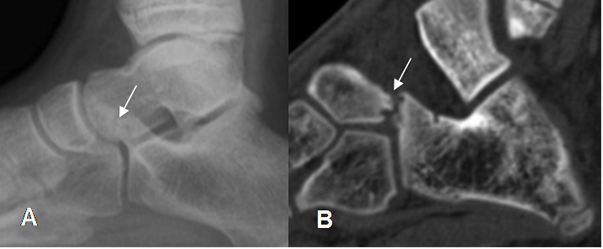

En la Rx simple y el TAC hay formación de puentes, en las coaliciones de tipo óseo. En las fibrosas y cartilaginosas los huesos están muy juntos y con irregularidad en sus contornos. (26). (Fig 135 A y B y 136 A y B).

Fig 135 A. Coalición del tarso.

A: Rx lateral. Pie plano y visualización de os trigonum.

B: TAC reconstrucción coronal y B: TAC axial. Coalición talocalcánea ósea interna.